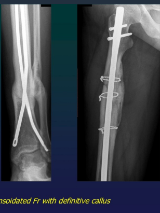

Pseudarthrosis

Callus

Hypertrophic

Fracture Healing

CALLUS GENESIS

Fibrino-proteic (1st 7 days)

Provisional fibrous (7-16 days)

Raw bone ( from day 16)

Definitive (6-12 maths)

Rx

Definitive: normal bone structure

Raw: NO structure

visible after 20-60 days